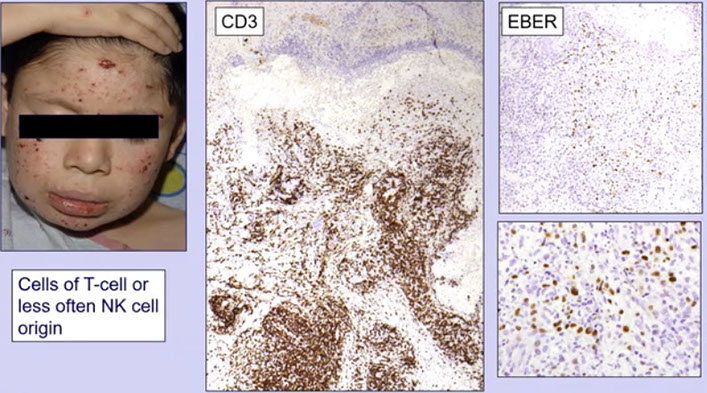

Ebstein-Barr virus (EBV) positive T-cell lymphoproliferative diseases of childhood

- Systemic EBV+ T-cell lymphoma of childhood

- Chronic active EBV infection of T- and NK-cell type, systemic form

- Hydroa vacciniforme-like lymphoproliferative disorder

- Severe mosquito bite allergy